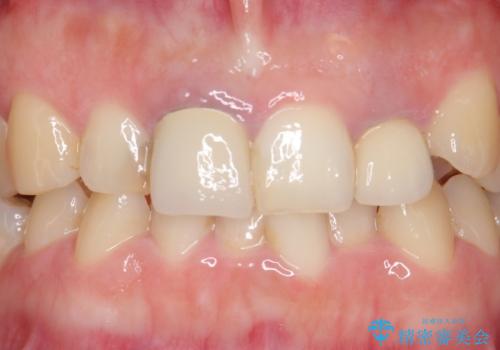

- 前歯の色や長さ、歯茎との隙間の金属が気になるのでセラミックで治療したいといらっしゃった方の症例です。

見た目改善のため、前歯4本をオールセラミッククラウン(スペシャル)で補綴しました。

右上1と左上2は再根管治療を行っております。